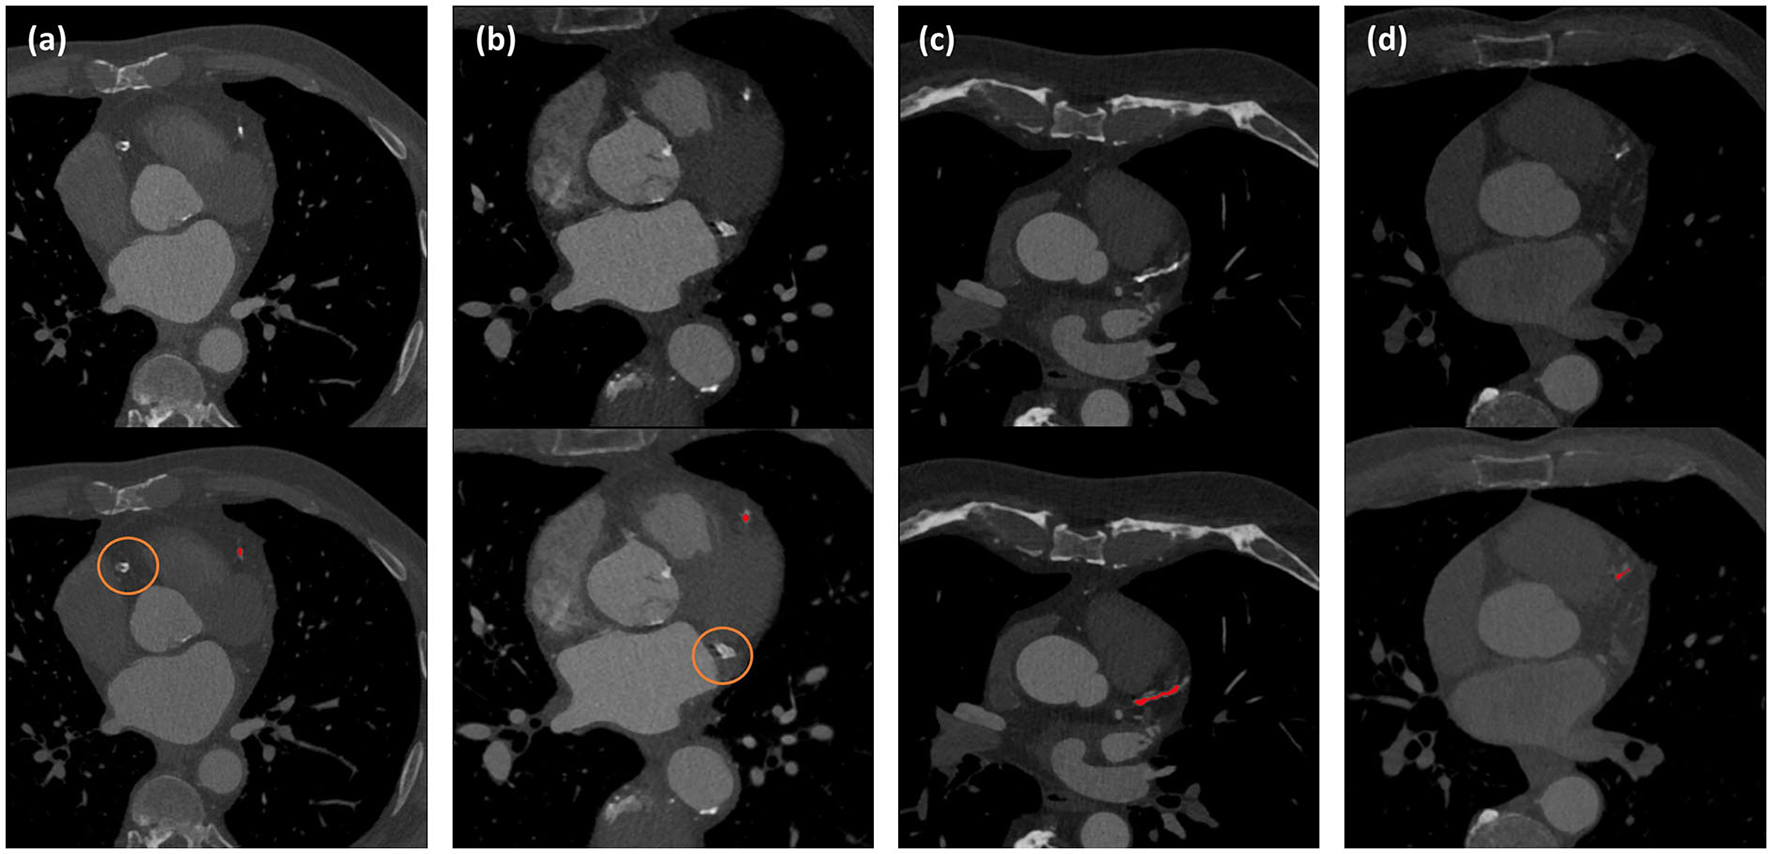

Coronary CT angiography slices and corresponding automatic CAC detections for two outliers cases (marked orange in Figure 3) are shown in Figures 4a,b. In addition, two representative cases from the labeled CCTA test set are shown in Figures 4c,d. For lesion-wise evaluation, the proposed method achieved an average sensitivity of 0.79 and FP lesion per scan of 1.06. The correlation between the number of automatically detected and manually annotated reference lesions was 0.69.

Figure 4

Automated CAC detection results in CCTA scans of four patients. The images in the first row show CCTA slices and the detected CACs are shown as overlay in the second row. Panels (a) and (b) illustrate the two largest outliers shown by orange dots in Figure 3, and false negative CAC are indicated by orange circles. Panels (c) and (d) show two cases with correct automatic CAC detections.

Retrospective analysis of the outliers shown in Figures 3 and 4 showed that in one case, a large CAC in the RCA (625 mm3) was detected by the CNN but removed in the FP reduction stage because its volume exceeded the maximum expected CAC volume. In the other case, large CAC in LCX (313 mm3) was not detected by the CNN. In our training set, median (Q1, Q3) CAC was 7.1 (1.6, 29.2) mm3 and 95th percentile was 188 mm3. This shows that the volumes of our false negatives substantially exceeded CAC examples in the training set. Adding examples of large CAC lesions in the training set or learning specifically focused on rare CAC examples might improve the performance.